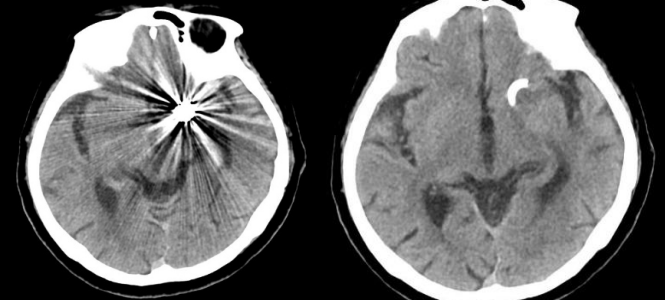

术后即刻影像显示动脉瘤栓塞满意,后交通动脉血流保存,血管通畅(蓝色及白色部分示动脉瘤完全填塞)

出院时头部CT检查未见缺血病灶